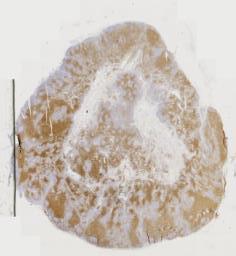

大体所见: (腹壁肿物)淡黄不整形组织一块,大小为2.2*1.4*1cm,切面灰黄,质中。

免疫组化: 阳性表达:S100、CD68、CyclinD1、Lambda、Kappa。MUM1.阴性表达:CD34、SMA、ALK(5A4)、CD1a。其他:Ki67(+,约5%),P53(+,野生型)。